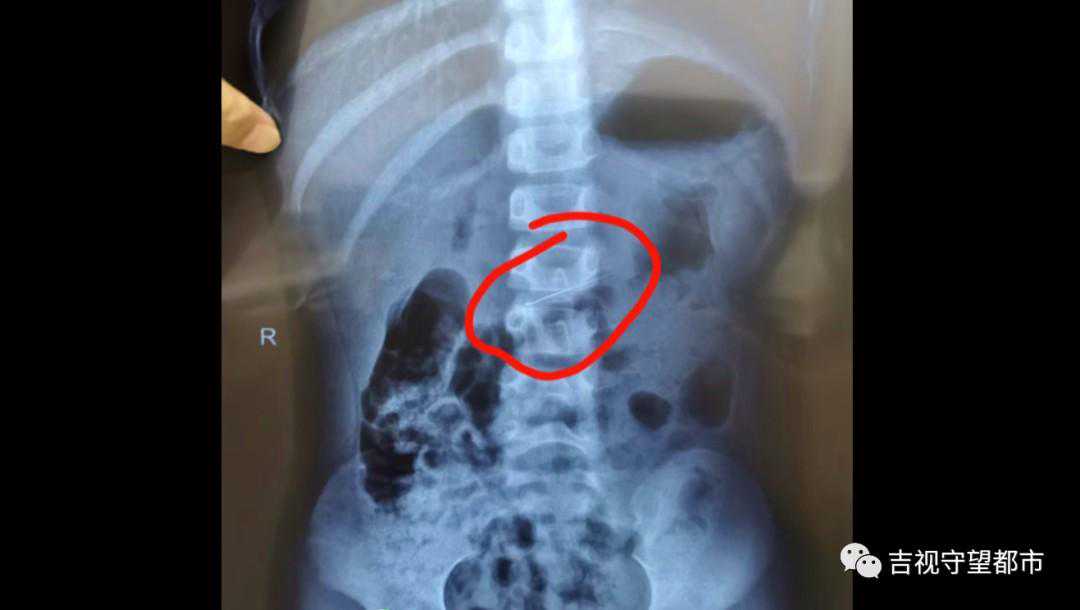

据家属描述,孩子误吞的这根修牙针长约4厘米,又细又尖,情况紧急,医生马上为患儿做了鼻咽镜,结果并未发现修牙针,怀疑针已经进入到消化系统。随即,院方马上为患儿安排拍片,最终在胃里发现了修牙针。

这个取出过程中,我们就需要保护这种消化道黏膜,因为那个针特别尖锐,取出的过程中,如果要是再刺伤这个消化道黏膜,可能会造成二次损伤,所以我们当时就在内镜前端装了一个透明帽,然后用这个透明帽把这个针放到这个透明帽里,这样就把黏膜保护起来,所以取完之后,孩子的消化道黏膜没有任何损伤。

仅3分钟,医护团队就将这根4厘米长的修牙针成功取出,使患儿转危为安,目前已经出院。